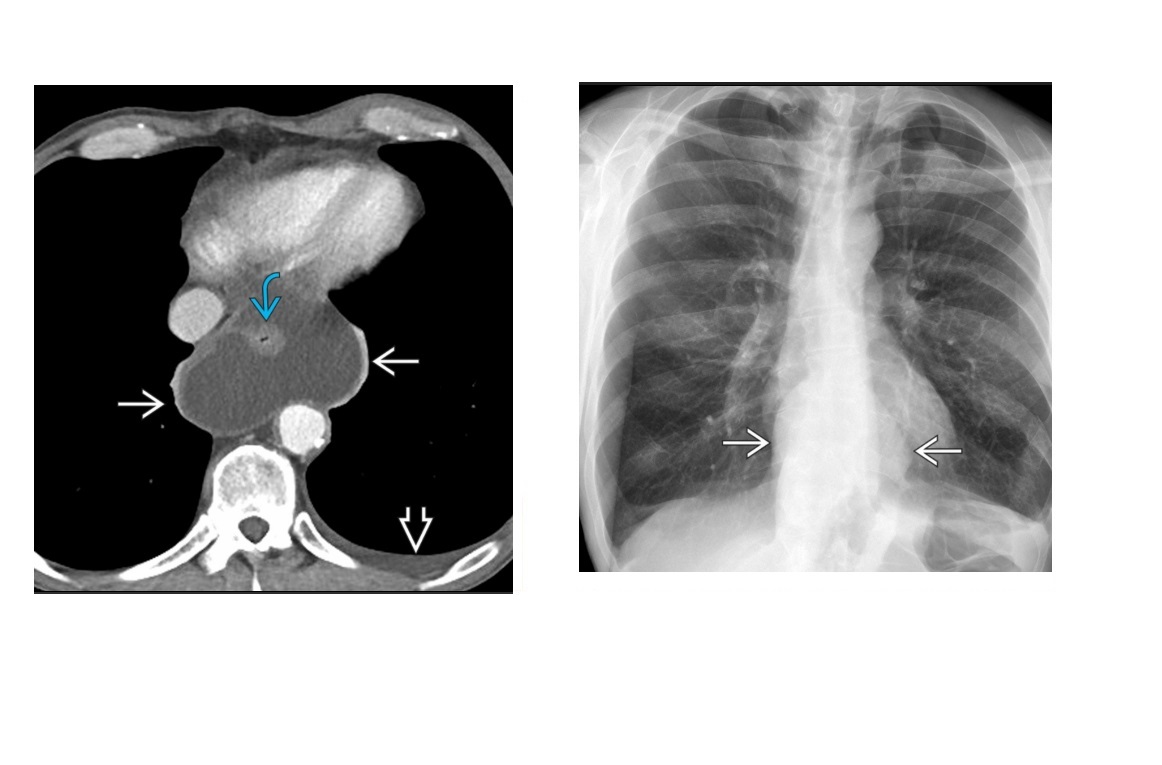

Sigmoid Vovulus Inverted U shape Ahaustra Coffee bean - cleft is double thickenss of opposed bowel loops Directed toward right upper quadrant (RUQ) or left upper quadrant (LUQ); Look for - Gas in proximal small bowel and colon Abscence of air in rectum Tend to be older patients Mx with rectal decompression

60